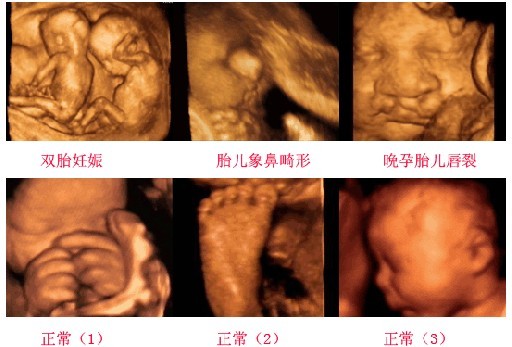

四维彩超超越了传统超声的限制,能够多方位、多角度观察宫内胎儿的生长发育情况,为早期诊断各种胎儿先天性体表畸形和发育异常提供准确全面的科学依据。

四维彩超鉴定的疾病:

1.胎儿面部畸形:如唇腭裂等。

2.神经系统:无脑儿、脑积水、小头畸形、脊柱裂及脑脊膜膨出。

3.消化系统:脐部肠膨出、内脏外翻、肠道闭锁及巨结肠等。

4.泌尿系统:肾积水、多囊肾及巨膀胱、尿道梗阻。

5.其它畸形:短肢畸形,联体畸形,唇裂、四心腔。

6.羊水过多、过少等。

四维彩超能清楚直观地显示胎儿面部情况及其相互关系,尤其是能够动态、多角度地观察宫内胎儿的颜面部、肢体的发育情况,甚至可以动态地观察到胎儿在母体里的状态,看到宝宝打哈欠、揉眼睛等可爱的动作。